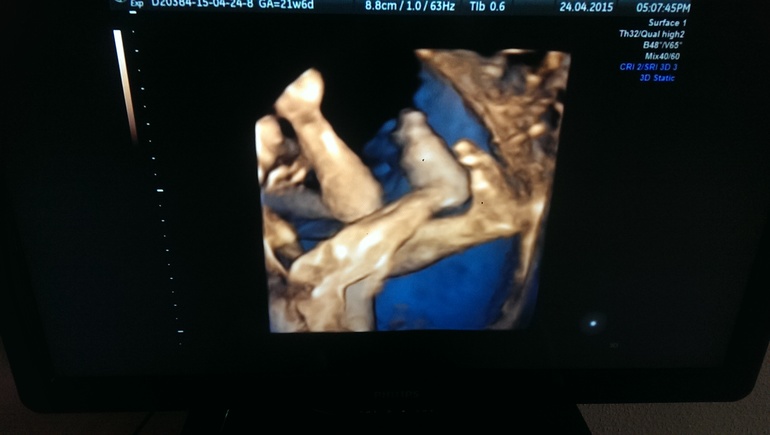

УЗИ, КТГ, доплерНа день рождения мужу решила подарить мужу поход на 4д узи :) Чтобы наконец познакомился с дочкой, пиночками радовать она его не спешит :) Узист сказал, что девочки обычно закрываются ручками всячески, но попросил ее папе в честь др показаться :)) Моя девочка папу порадовать решила как следует! Улыбалась, лежала нога на ногу, ротик открывала! Показала образцовый "фейспалм", позу мыслителя, пуповиной поиграла :) Ну и подтвердили, что 100% доча, что все у нее хорошо, весит 464г уже! Узист-мужчина так мило радовался с нами каждой ее улыбке, каждой красивой позе, впечатления отличные :) Муж довольный! Сидел улыбался :)Делали в Парацельсе на Большакова, если землячкам интересно :) Ну и пара фоток (пришлось включать на иксбоксе диск, сидиром отказался воспроизводить диски) :)